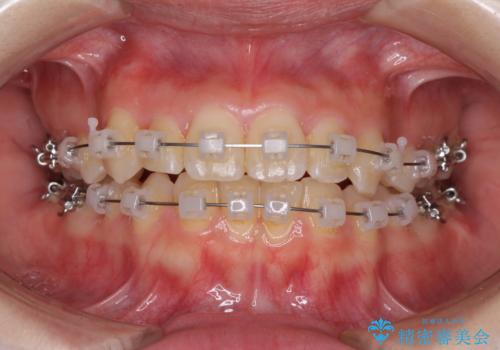

- 矯正装置

- クリアブラケット

- 治療期間

- 2年2ヶ月

- 治療回数

- 10-30回